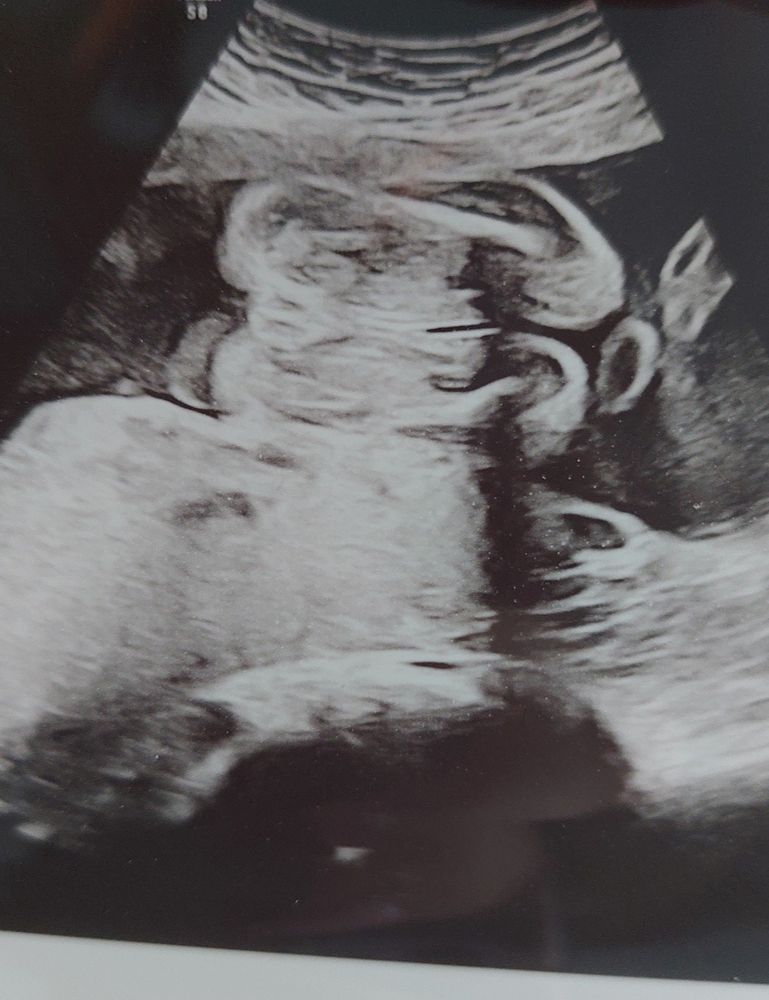

Всем привет! Первая моя беременность, на узи сказали что девочка, но все равно есть какие-то сомнения. На первом кзи в 12 нелель предположили мальчика, потом в 13.5 недель делала скрининг на генетические аномалии, в Германиион делается отдельно, то врач предположил на 90 процентов девочку. Пол нам не важен, просто интерес берет своё☺️ В 23 недель сделали второй скрининг, где врач говорит что девочка, может ли он ошибаться. Есть только такое фото))

Да,это девчуля🥰вон пирожочек такой )Это половые губы)

Врач говорит что это половые губы 😅 Думаю могла ли она ошибиться 🤷♀️☺️

Если то, на что я смотрю - половая принадлежность, то тогда девочка. Но честно, само фото вызывает вопросы, а с какой это вообще стороны 😅

Сама была удивлена такому ракурсу, врач говорит что это половые губы)

Алина Терёхина, ну если врач сказала, то тогда это оно. Она же в движении видела, ей понятно, где ноги, где голова😅. А так да, очень на половые губы похоже

Это девочка. Кофейное зёрнышко слева на фото четко просматривается 😉